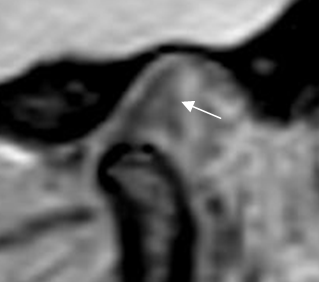

Fig 16. Sinequia.

RM sagital oblicua en GE, con boca abierta. La banda posterior está deformada y no se desplaza junto el cóndilo, por la presencia de adherencias.